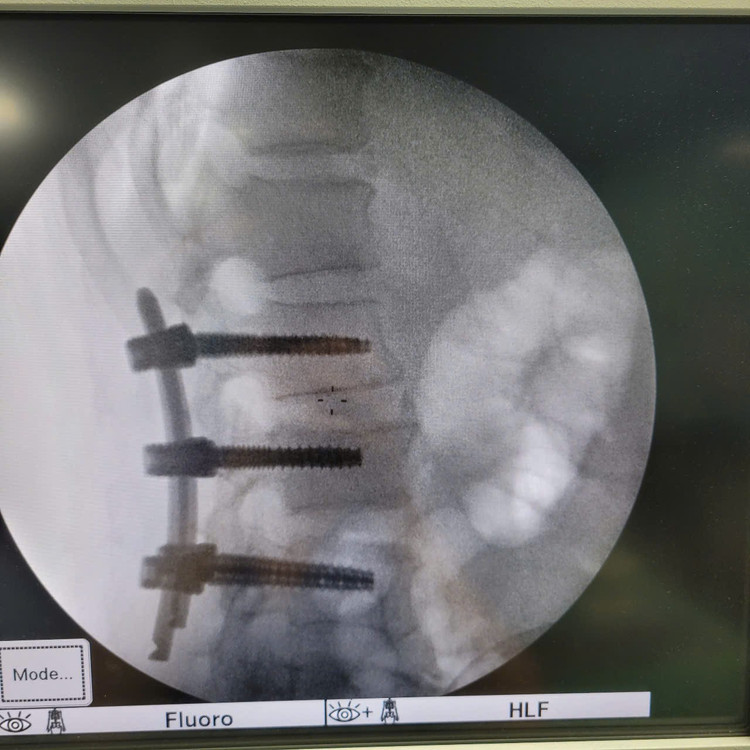

Các bác sĩ Khoa Ngoại Thần kinh – Chấn thương Chỉnh hình, Bệnh viện Hữu Nghị đã triển khai thành công kỹ thuật mới, phẫu thuật bắt vít cột sống qua da ít xâm lấn cho bệnh nhân nam 59 tuổi bị chấn thương cột sống, vỡ đốt sống L2 gây mất vững.

Bắt vít cột sống qua da.

Sử dụng hệ thống máy C-arm, dẫn đường hình ảnh (navigation) để đặt vít chính xác tuyệt đối, tránh tổn thương tủy sống và rễ thần kinh.